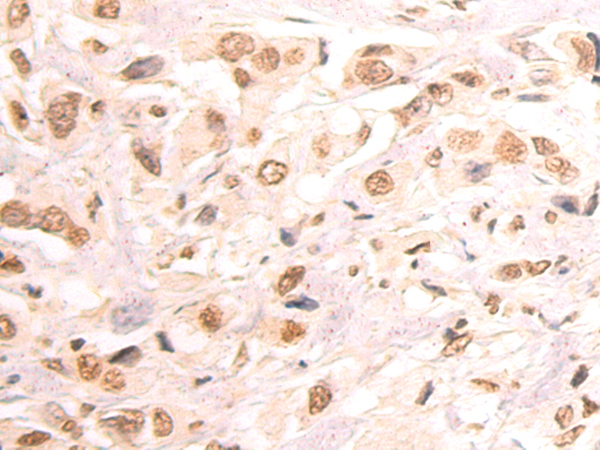

分类: 科研抗体货号: P12875别名: DR11; HH14; BRWD2; WDR15应用: WB,IHC反应种属: Human